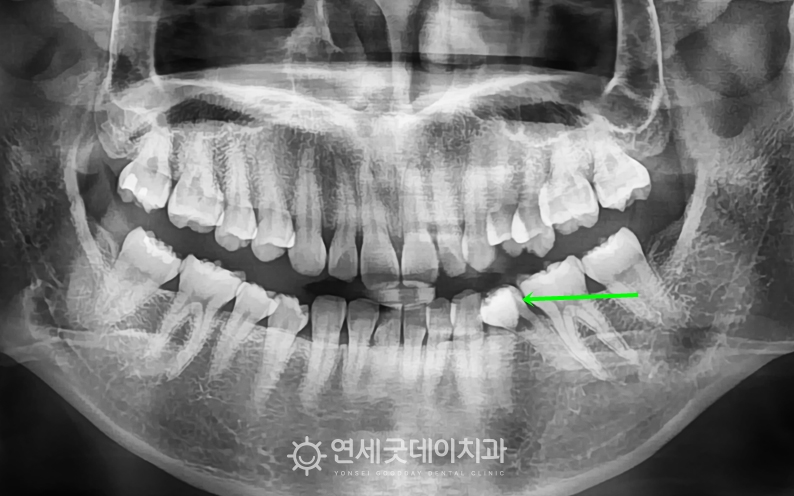

하지만 #35 치아가 쓰러지면서 또 한 가지 주의 깊게 살펴볼 부분은 ‘과개교합’입니다. ▲ 치료전 안모 (촬영시기 : 2022년 10월) 환자분은 과개교합, 쓰러진 치아로 인한 인접치의 정출 따라서 부분교정의 한계점에 대해 충분히 설명드린 후 ▲ 과개교합 교정 후 엑스레이 (촬영시기 : 2024년 3월) 약 1년 6개월의 인비절라인 교정이 마무리되었습니다. 기울어진 치아는 정상적인 위치로 올바르게 세워졌으며 ▲ 과개교합 교정 종결 (촬영시기 : 2024년 3월) 윗니의 높이와 각도가 개선되면서 아랫니가 정상적으로 드러나고, ▲ 치료 후 안모 (촬영시기 : 2024년 3월) 웃을 때마다 과도하게 드러났던 거미스마일도 ▲ 치료전후 비교 (촬영시기 : 2022년 10월 / 2024년 3월) 과개교합은 턱관절 불편감이나 저작 불편으로 이어질 수 있어 과개교합을 교정함으로써 증상을 완화하고 그동안 치료 받으시느라 고생 많으셨습니다. ^^ ※ 모든 사진은 본인의 동의를 얻어 동일조건에서 촬영하였으며 |